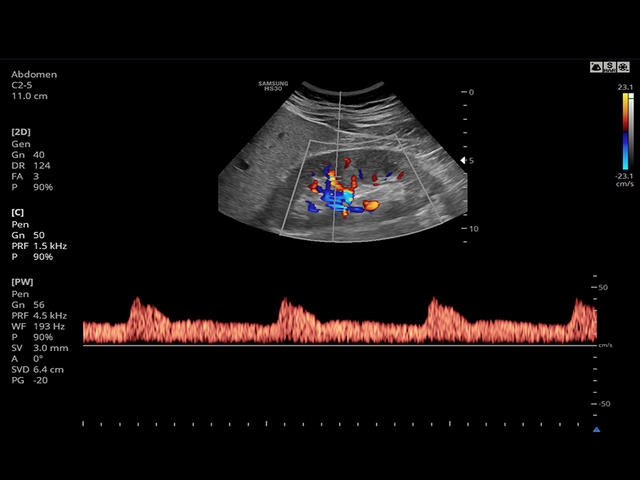

- PW - импульсно-волновой допплер, steering - изменение допплеровского угла в режимах CD и PD, автоматический анализ допплеровских кривых.

Сосуды брюшной полости: автоматическая, полуавтоматическая, ручная трассировка доплеровского спектра; ПСС, КДС, %СтПлощ, %Ст Диам, площадь сосуда, диаметр сосуда, объемный кровоток.